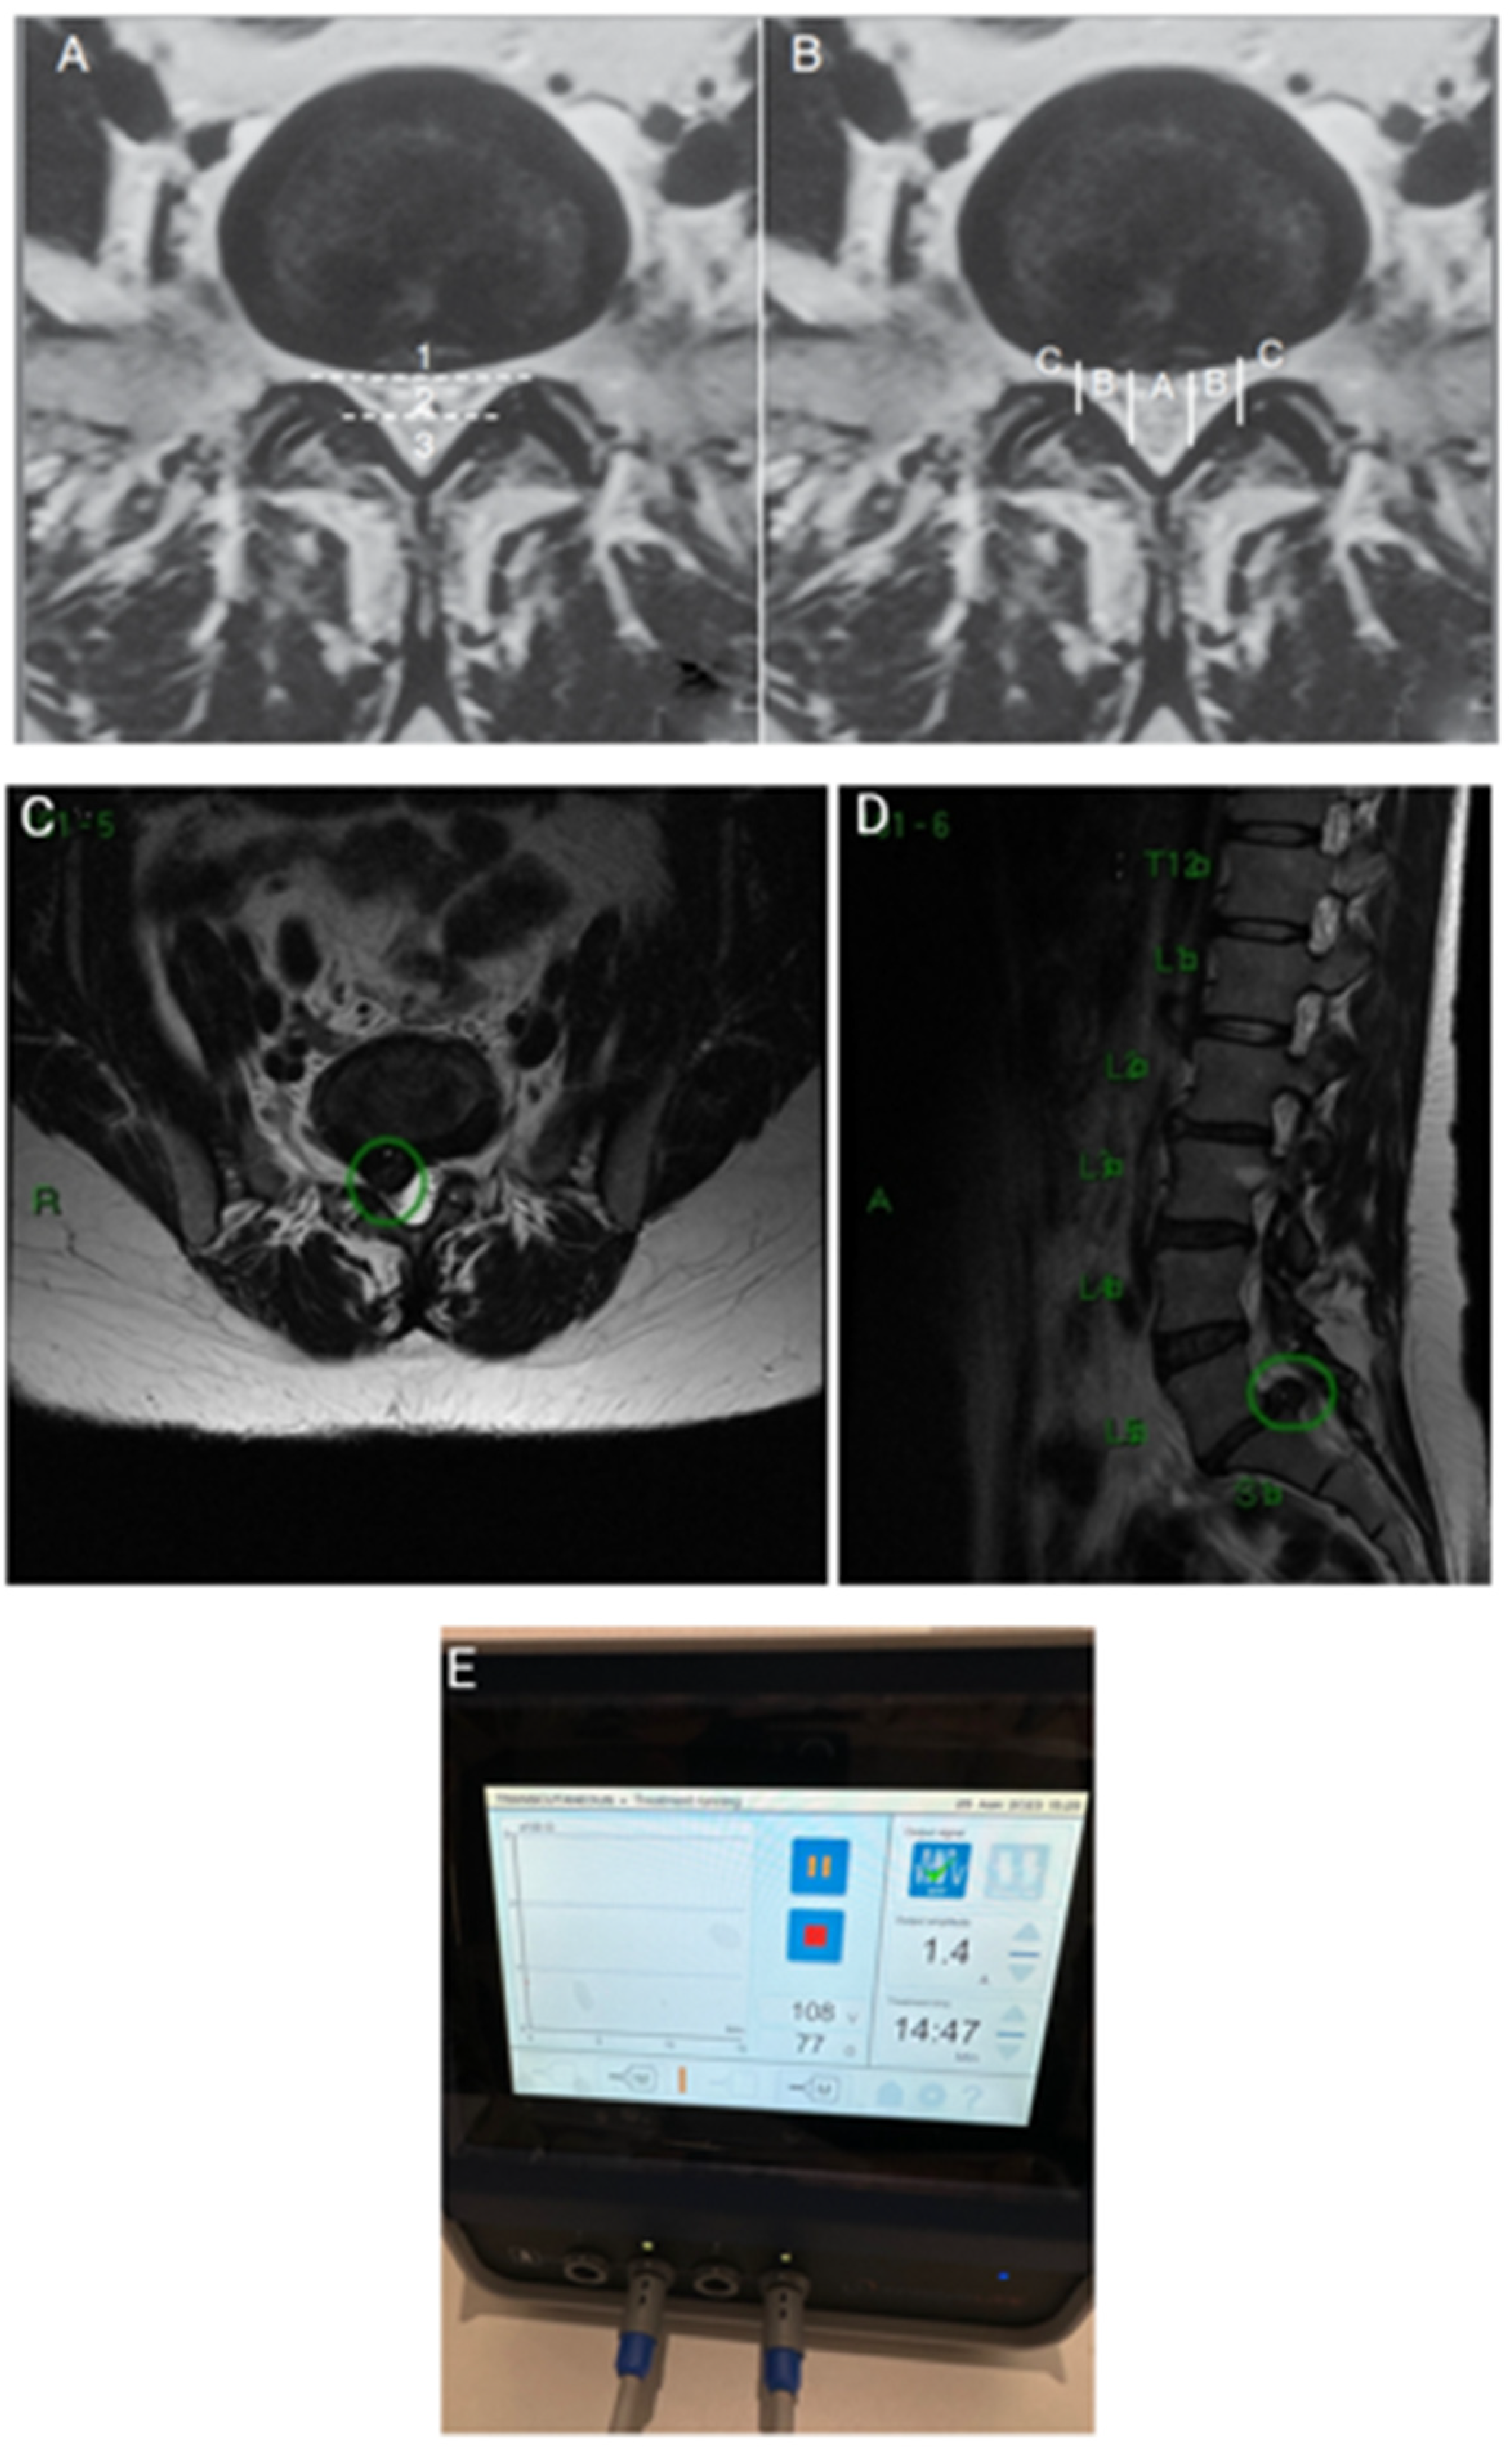

J.A.R.G.M.A., a 43-year-old woman, presented with back pain radiating to the left posterior thigh, without numbness. Her pain worsened while sitting and she struggled to walk properly or maintain an upright position for prolonged periods. Despite the significant lumbar L5-S1 disc herniation identified on her MRI scan (Figure 3A), there were no clinical changes in strength or reflexes. The patient expressed strong concerns about surgery and invasive procedures, opting against surgery despite recommendation.

We offered her the option of transcutaneous pulsed radiofrequency (PRF) using a Spring2® generator with large patches. The PRF STP was set at an amplitude of 1.0A and 61V for 15 minutes (Figure 3C). A total of three sessions were performed, with the second session two weeks after the first, and the final session 45 days after the initial treatment.

Figure 3. A) Huge L5-S1 central left disc herniation; B) MSU classification 3B, Pfirmann IV; C) Large patches positioned for the TCPRF STP in order to apply the electromagnetic field from the pain origin to the irradiation site.